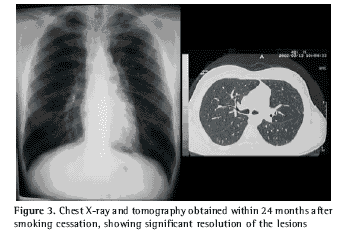

The patient was advised to stop smoking and, due to his excellent general condition, no other treatment was advised. Smoking cessation was confirmed at each control visit by serial measurements of carbon monoxide in exhaled air (MicroCO - Micro Medical Ltd, Rochester, Kent, UK). Serial follow-up visits confirmed complete remission of the symptoms and, within three months after smoking cessation, significant radiological improvement was observed. A second high-resolution computed tomography confirmed the favorable evolution and the tendency was maintained up to the last control tomography, performed at 24 months after smoking cessation (Figure 3).

In the present case, there was a clear temporal relationship between smoking cessation and clinical-radiological improvement, confirmed by serial assessments. We observed objectively quantifiable radiological improvement within approximately three months after smoking cessation, which leads us to believe that the present case contributes to the hypothesis that smoking cessation promotes the favorable evolution of the disease.